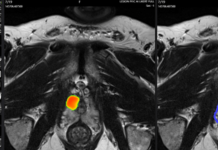

Kardium’s Globe mapping and ablation system features a catheter with a 122-electrode array and advanced software. The platform enables rapid pulmonary vein isolation, high-definition mapping and the ability to ablate anywhere in the atrium. All of these capabilities combine in one single catheter.

Globe catheter sensors provide proprietary Contact maps to identify electrodes in contact with cardiac tissue. This helps to ensure therapy for AFib is effectively delivered.